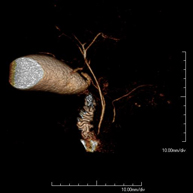

- Abdominal aorta MRI angiography

A non-invasive diagnostic test that involves studying the abdominal aorta, obtaining high-definition anatomical images using an electromagnetic field and radio waves (with transmitter and receiver). The use of paramagnetic contrast (gadolinium) is essential. However, it is a radiation-free procedure. The quality of the images allows for 2D and 3D reconstructions. It is indicated in patients with vascular disease (atherosclerosis), aneurysm studies, pre-surgical studies of lesions adjacent to the abdominal aorta as a vascular ‘map’, etc.

- Aortic-iliac MRI angiography

A non-invasive diagnostic test that involves studying the abdominal aorta and iliac arteries, obtaining high-definition anatomical images using an electromagnetic field and radio waves (with transmitter and receiver). The use of paramagnetic contrast (gadolinium) is essential. However, it is a radiation-free procedure. The quality of the images allows for 2D and 3D reconstructions. This test is particularly recommended as a pre-surgical study (vascular map) prior to percutaneous or surgical interventions on the abdominal aorta and iliac arteries, as a complementary study in patients with lower limb ischaemia, etc.